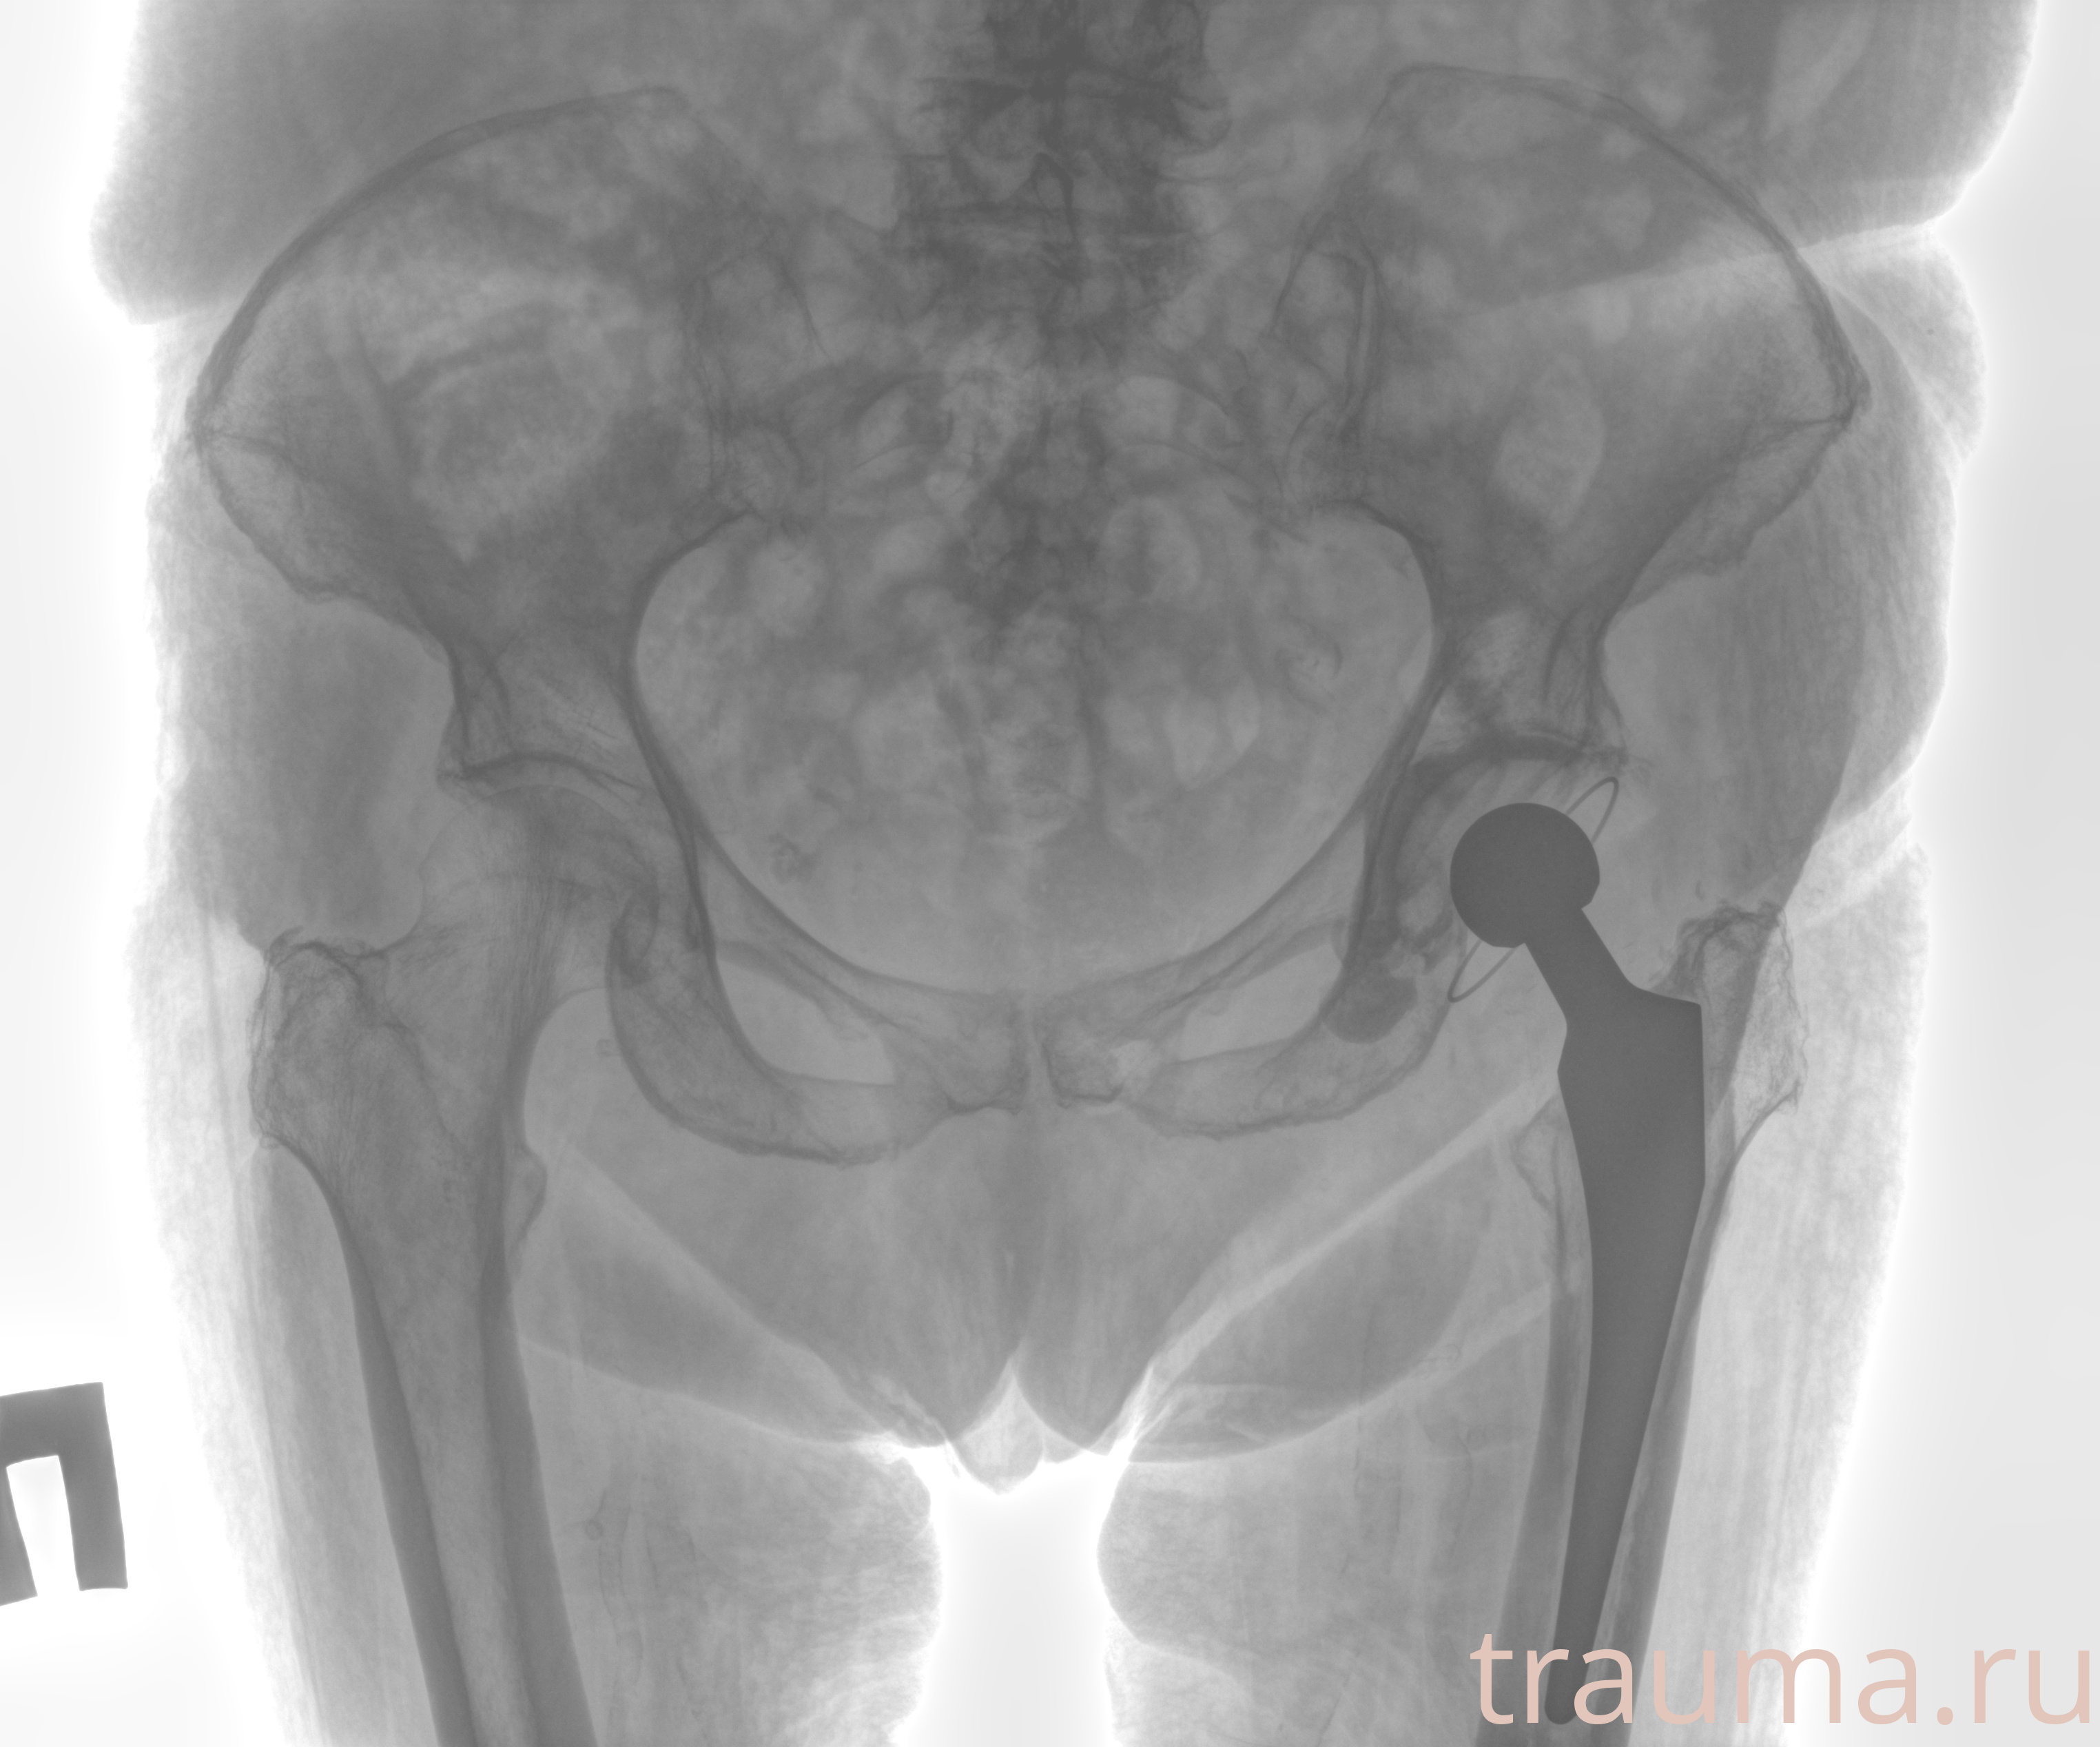

Рентгенограммы

Рентген на дому: по вашему адресу приезжает врач-рентгенолог, травматолог-ортопед с мобильным рентгеновским аппаратом, проводит диагностику травмы или заболевания, делает необходимые рентгенограммы, дает рекомендации по дальнейшему лечению. Получить качественные снимки в домашних условиях возможно благодаря уникальной методике, разработанной МосРентген Центром для института  Склифосовского

при переломе шейки бедра и пневмонии от компании МосРентген Центр - партнера Института имени Склифосовского